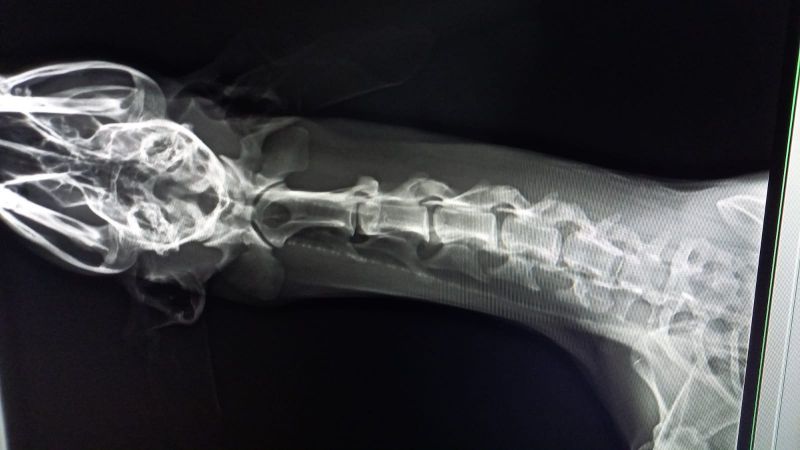

Pilar hat Esperanza bereits zu zwei Tierärzten in Zaragoza gebracht. Die Galga läuft seltsam und schrie regelrecht vor Schmerzen, insbesondere wenn sie am Hals angefasst wird. Es ist schrecklich, die arme Galga so leiden zu hören. Leider wissen wir aktuell noch nicht, was Esperanza hat. Beide Tierärzte haben unterschiedliche Vermutungen - es könnte eine alte Verletzung, aber auch ein Tumor an den Halswirbeln sein. Genauers kann nur ein MRT zeigen, welches auch in Spanien sehr kostenintensiv ist.